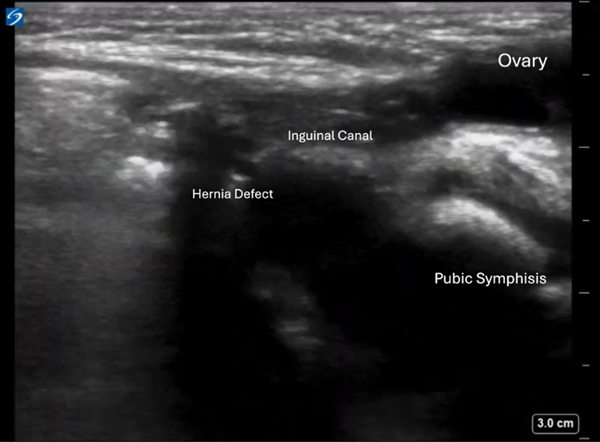

Image 2: Sagittal view. Hernia defect visualized with the hernia sac going towards the labia containing a heterogeneous mass, which appears to be an ovary.

The contralateral (left) pelvis was scanned, showing a similar structure consistent with a normal-appearing ovary in its expected location. On returning to the affected side, the right ovary was absent from the pelvis. The inguinal mass was identified as the right ovary, herniated into the inguinal canal.